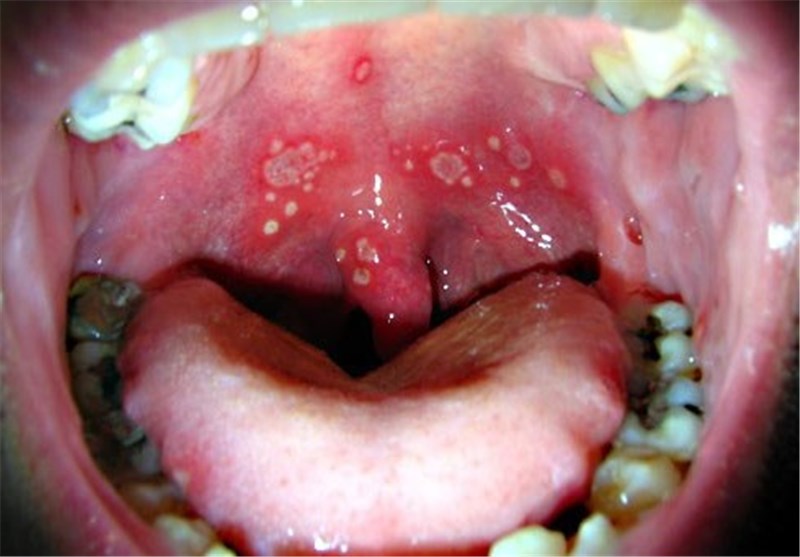

زخم‌های دهانی که منجر به سرطان می‌شود+توصیه‌ها

خبرگزاری تسنیم: رئیس سیزدهمین کنگره بین المللی جراحان دهان، فک و صورت ایران نسبت به زخم‌های دهانی که منجر به سرطان می‌شود، هشدار داد.

کریمی گفت: شایع ترین سرطان ناحیه دهان فک و صورت سرطان سلول‌های سنگ فرشی مخاط دهان است که حدود 90 درصد سرطان‌های ناحیه فک و صورت، سرطان سلول‌های سنگ فرش مخاط دهان هستند و این سرطان عوامل ایجاد کننده دارند از جمله  مصرف دخانیات که احتمال ایجاد سرطان را افزایش می‌دهد، مصرف مشروبات الکلی یا هر چیزی که مخاط دهان را تحریک کند مانند استفاده از دست دندان‌هایی که خوب ساخته نشدند و در دهان لق هستند و ممکن است به مرور زمان به دلیل لقی ایجاد زخم کنند که اگر این دست دندان درست نشود در دراز مدت ممکن است منجر به سرطان شود.

وی هر عاملی که منجر به تحریک مخاط دهان شوند از جمله سیگار، الکل و همچنین مصرف متداوم مواد غذایی تند و تیز را عامل اصلی در ایجاد سرطان دانست و گفت:  دندانهایی که بنا به دلایلی شکسته اند و یک تیزی در دندان ایجاد شده است که این تیزی باعث زخم در زبان می‌شود و اگر آن دندان درمان نشود در دراز مدت ممکن است این زخم به سرطان تبدیل شود بنابراین این سرطان که شایع ترین سرطان‌های ناحیه فک و دهان است خودش را با یک زخم نشان می‌دهد و زخم در مراحل اولیه بدون درد است و متاسفانه مریض به پزشک مراجعه نمی‌کند و به مرور زمان هم این زخم از بین نمی‌رود و خیلی مواقع مردم این زخم‌ها را با آفت اشتباه می‌گیرند ولی آفت که شایع ترین ضایعه مخاطی دهان است اگر هیچ درمانی هم انجام نشود ظرف یک تا دو هفته خود به خود خوب می‌شود ولی زخمی که در دهان بوجود آمده است بعد از یک تا دو هفته خوب نمی‌شود و حتی با برطرف کردن عامل ایجاد زخم  باز زخم خوب نمی‌شود، بنابراین بیمار حتماً باید به متخصص مربوطه مراجعه کند تا این زخم بیشتر مورد بررسی قرار گیرد.

این عضو هیات علمی دانشگاه علوم پزشکی تهران گفت: اگر این سلول‌های سنگ فرشی مخاط دهان زود تشخیص داده نشده است و به موقع درمان نشوند به مرور زمان خیلی بزرگ می‌شوند و ایجاد مشکل برای غذا خوردن و حتی نفس کشیدن می‌کنند و این سرطان‌ها اگر به موقع درمان نشوند غدد لنفاوی گردن را درگیر می‌کنند و اگر باز درمان نشوند سایر نقاط بدن را درگیر می‌کنند، بنابراین پیشگیری این سرطان‌ها خیلی مهم است و هر زخمی که در دهان وجود دارد باید جدی گرفته شود و افراد باید به متخصص جراح فک و صورت مراجعه کنند.